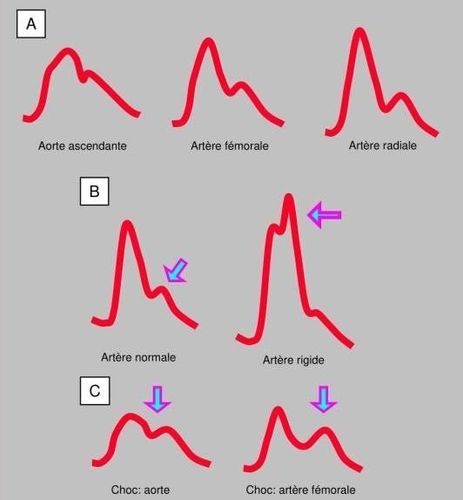

Trong phẫu thuật tim, ống thông động mạch được đặt một cách vô trùng trước khi gây mê, ngoại trừ ở trẻ em. Sự lựa chọn vị trí đâm kim phụ thuộc vào khả năng kỹ thuật, loại phẫu thuật, sự can thiệp cho tuần hoàn ngoài cơ thể (THNCT) và tình trạng huyết động.

- Động mạch quay: dễ sờ, sạch, nhưng giá trị đường cong và áp suất phụ thuộc vào co mạch (vùng cơ xung quanh động mạch);

- Động mạch đùi: dễ tiếp cận nhưng khó duy trì hơn trong dài hạn; độ tin cậy tốt nhất của đường cong và các giá trị áp lực (động mạch đàn hồi) và gần nhất với động mạch chủ; có thể đặt nhanh trong trường hợp bị sốc;

- Các động mạch khác: trụ, cánh tay, nách (lựa chọn thay thế trong trường hợp thất bại nhiều lần).